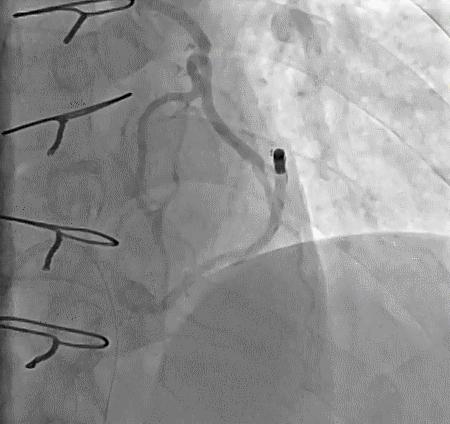

2014年,Patel T等首先采用球囊辅助通过技术(Balloon-assisted tracking,BAT),用于通过桡动脉途径中扭曲、细小节段(包括严重痉挛节段)(图1-2)。

图1

图2 BAT技术应用实例1。52岁女性患者冠脉严重痉挛(A),注射2次鸡尾酒后仍未缓解(B),采用BAT技术(C),顺利介导7F指引导管通过桡动脉严重痉挛节段(D)